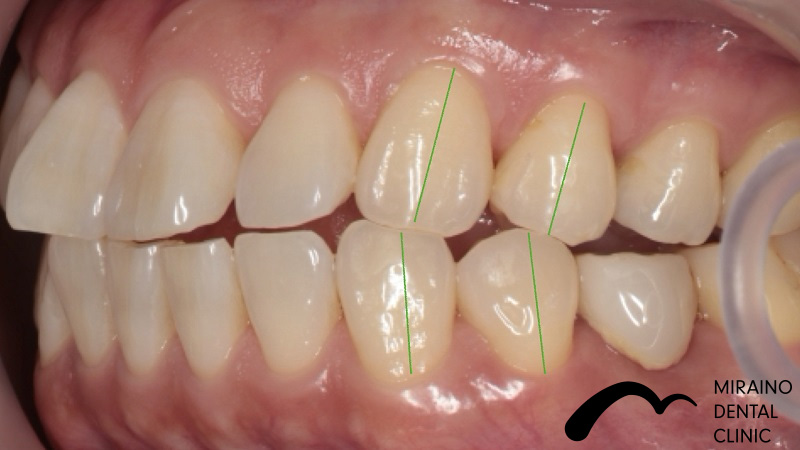

無菌的根管治療→被せ物・メタルフリークラウンの症例

Case1

| 施術名 | 無菌的根管治療 |

| 治療の概要 | 噛んだ時の違和感・歯ぐきにできものができるということで来院されました。 過去に神経の治療を行なっている場所の再発でした。 治療中の唾液による感染を防止するため、 ラバーダムを用いて無菌的に歯の根の中・根の先の感染の除去治療を行いました。 6ヶ月経過観察後、感染再発の症状が見られなかったため、 汚れのつきにくい素材で被せ物を装着しました。 |

クリックして詳細を表示

| 施術の内容 | 歯の根の中・根の先の感染の除去します。 ラバーダムを用いて唾液による感染のリスクを排除し無菌的な治療を行います。 感染・炎症の所見が無くなれば抗菌作用のある材料で根っこの通り道を封鎖します。 ラバーダム を用いて唾液による感染のリスクを排除し無菌的な治療を行います。 |